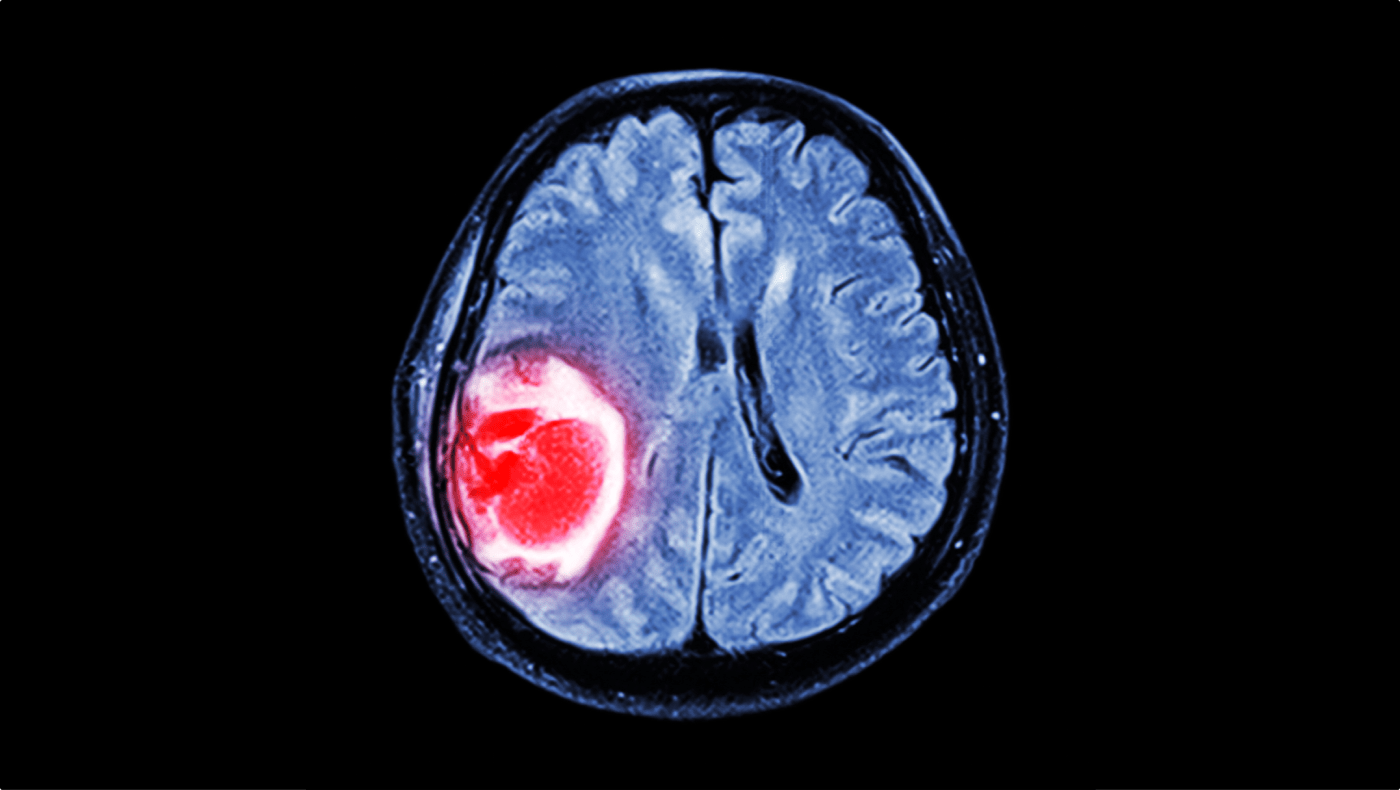

Tumör i hjärnan syns som ett rött område på en röntgenbild av hjärnan.

Tumör i hjärnan. Läs mer om bland annat symtom på hjärntumör här.